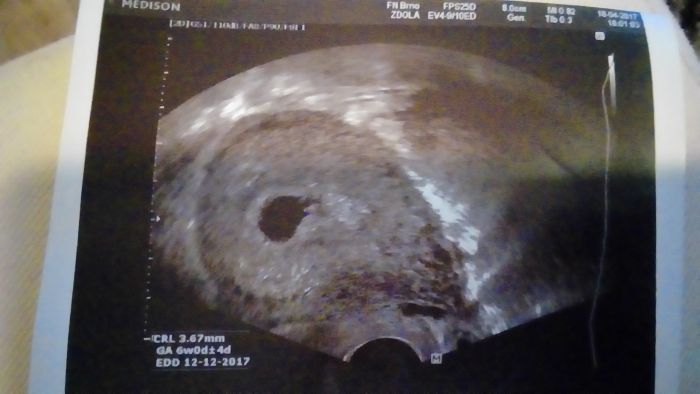

Ahoj holky tak je vše ok a na dobré cestě, srdíčko už tam bylo i nějaká odezva..další kontrola 23.května, tak mě to uklidnilo :-) samo říkal že vyhrané ještě nemám ale to je jasné do toho 12 týdne..

[990699] moc to tam nejde vědět ale je to tam na pravé straně ta fazolka